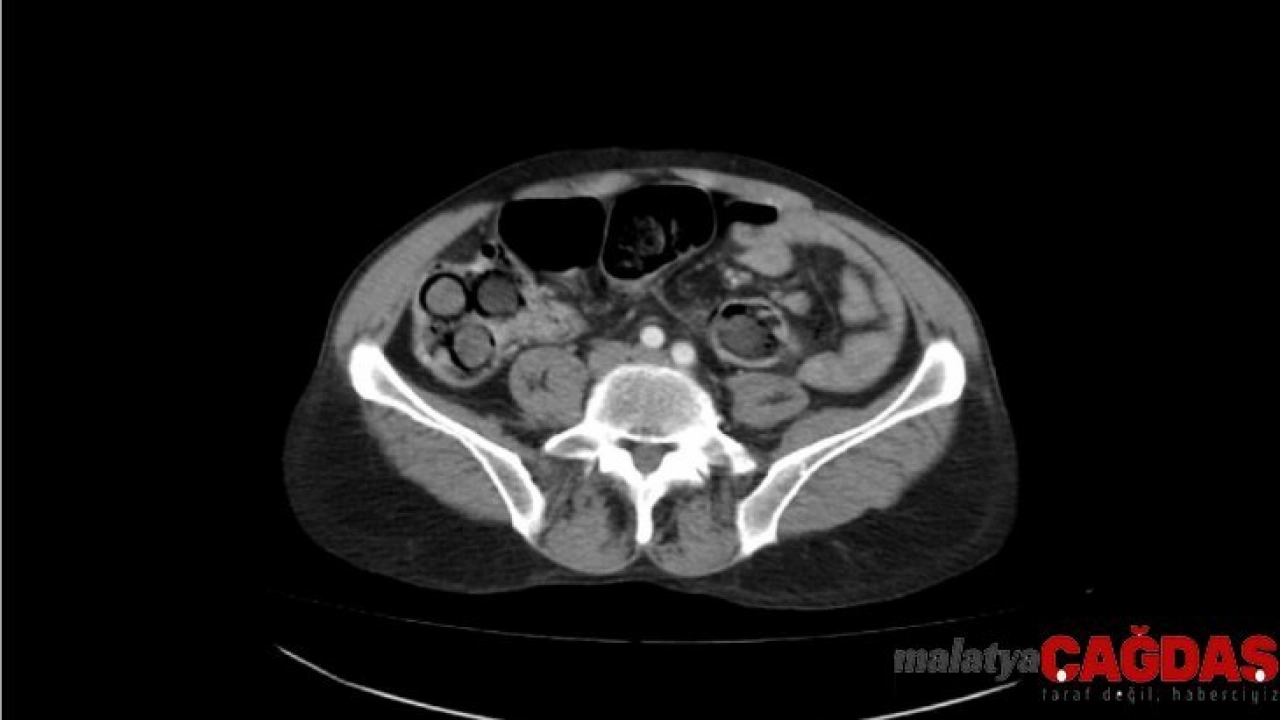

Polis, şahsın midesinde eroin olabileceğinden şüphelenip hemen hastanenin gastroenteroloji bölümüne götürdü. Burada tomografisi çekilen midede, sosis büyüklüğünde paketler tespit edildi. Ancak polis, emin olmak için daha sonra şahsa endoskopi işlemi de yaptırdı. Bu sayede ucunda ışıklı küçük bir kamera bulunan ve endoskopi adı verilen bir cihaz yardımıyla şahsın yemek borusu, mide, onikiparmak bağırsağı ve kalın bağırsaklarında 49 paket sosis büyüklüğünde paketler olduğu kesinleşti.